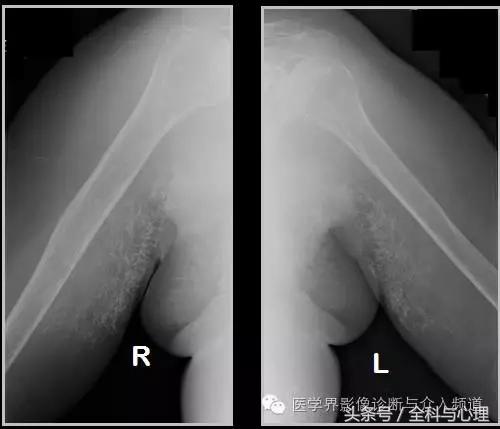

半月板钙化